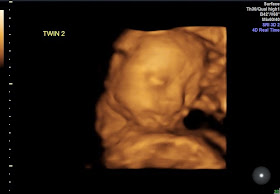

Baby girl was a different story and not only was she in an awkward position but she kept moving as well as having her umbilical cord across her face most of the time. She actually looks a bit grumpy compared to him in these pictures, especially the second one:

| You can see her umbilical cord cutting across under her chin like a necklace. |